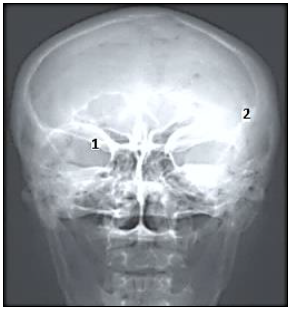

“Através do estudo anatômico, compreendemos a importância das imagens radiológicas do esqueleto axial e apendicular, sem distinção quanto à forma de aquisição, analógica ou digital.”

Com base na imagem radiológica apresentada, os números expostos referem-se, respectivamente, a quais estruturas anatômicas?